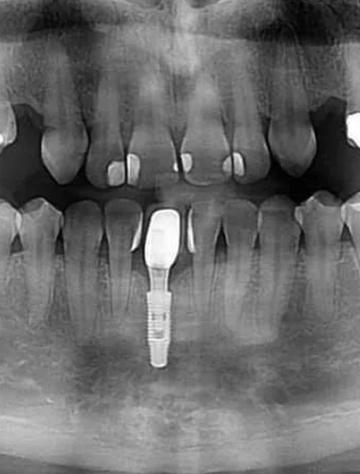

- 种植体位置: 确认种植体是否放置在理想位置。

- 骨结合情况: 观察种植体与周围骨组织是否良好结合(骨整合)。

- 主要影响是图像质量,而非安全。 高密度的金属种植体在CT图像上会产生金属伪影,即围绕种植体出现明亮的亮斑和暗区,可能会干扰对种植体周围骨组织、神经血管等结构的清晰观察。

- 专业口腔CBCT: 这是种植牙评估的首选,它的扫描范围小、分辨率高(尤其是骨组织)、金属伪影相对可控,能提供种植区域最精细的3D图像。